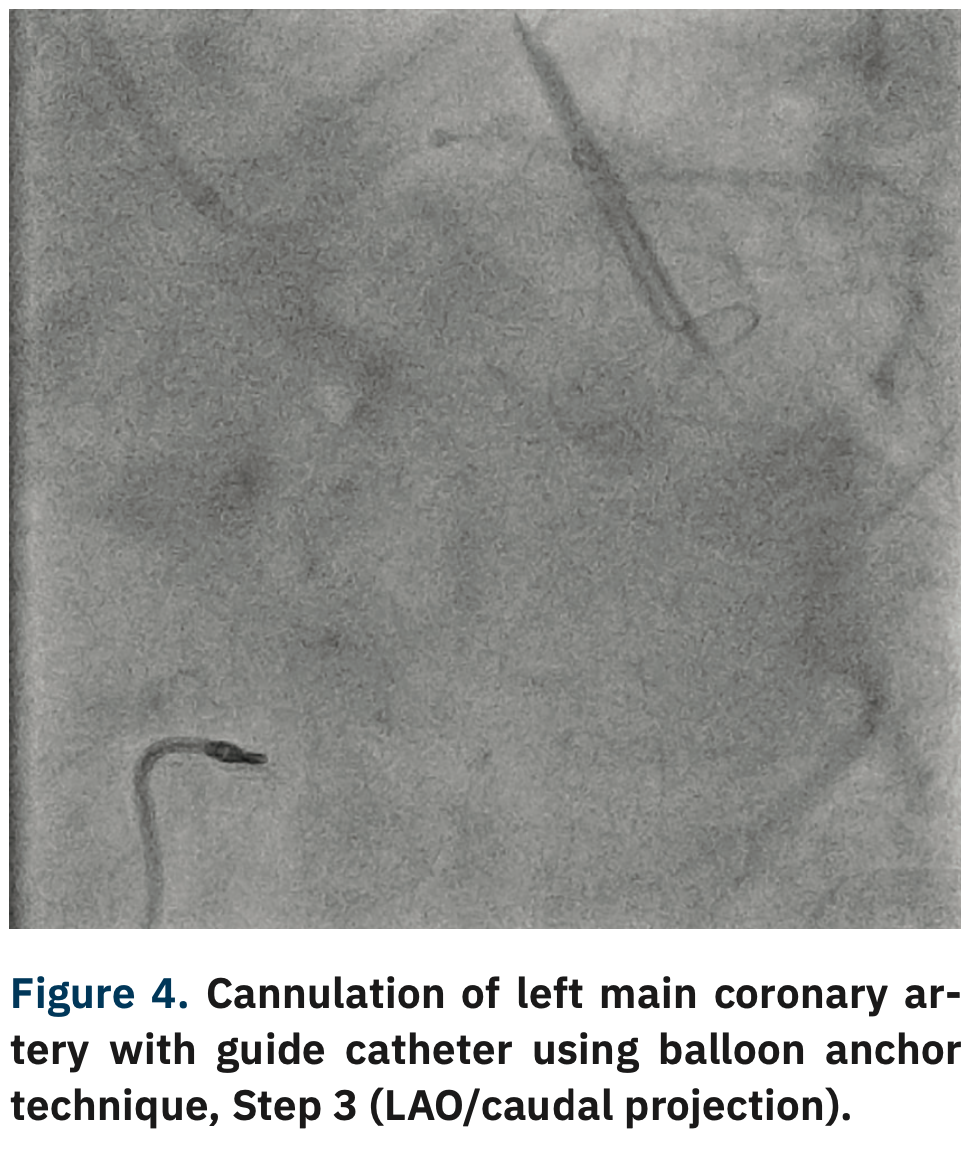

After gaining wire access to the LCx, support was increased by advancing a 5 Fr GuideLiner V3 guide extension (Teleflex) to the distal LM coronary artery. Unfortunately, even the combined support provided by the coronary guidewire and GuideLiner was not enough to allow engagement of the LM ostium with the guide. At this point, a NC Trek 2 mm x 12 mm balloon (Abbott Vascular) was advanced into the distal LM/proximal LCx and inflated to 5 atmospheres (atm) (Figure 2). With the help of this balloon anchoring, the guide catheter was gently lifted, then advanced into the ostial LM coronary artery (Figures 3-5). During this maneuver, gentle counter traction was placed on the shaft of our balloon catheter. After successful guide delivery to the LM coronary artery, the rest of the procedure was uneventful, with placement of a drug-eluting stent into the distal LM and proximal LCx with optimal angiographic result.